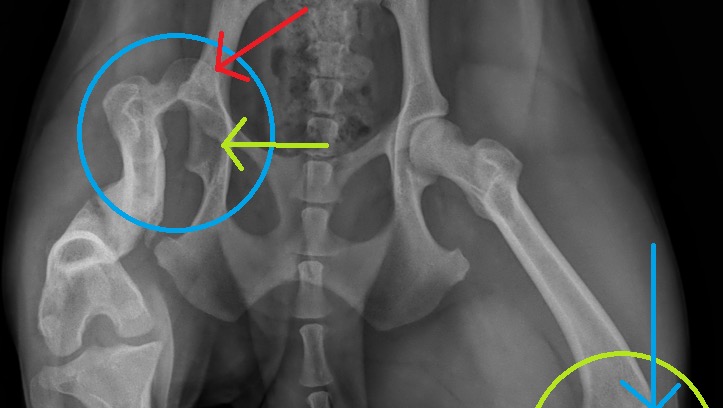

After the first day at our home, I noticed that she had a little bit of a limp and would sometimes lift one of her hind legs. We took her to the animal hospital that the rescue is connected with, and they took x-rays. The x-ray showed that she had a previous injury in her left hind leg, and it was a broken femur... a compound break. Also, the ball and socket showed trauma too. The femur showed signs of some healing, although the bones were not aligned. The theory is that she may have been hit by a car at one point. As a stray, she was living on the streets and somehow survived even with a broken leg.

Willow’s broken femur

Ball & socket of same leg